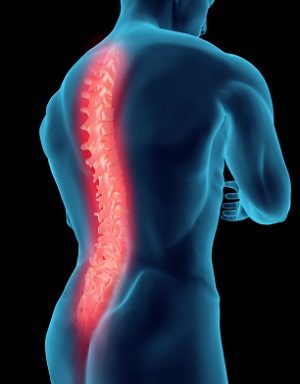

What is Spine Comprehensive Medicine?

Spine comprehensive medicine involves comprehensive care of acute or chronic neck or back injuries or conditions. It aims at minimizing your pain, making you as functional as possible and preventing future injury.

Conditions Covered under Spine Comprehensive Medicine

We provide effective care for spine conditions such as: